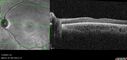

28 year old female Good vision since birth started wearing glasses at 2, denies trauma. She does have congenital nystagmus.

VA OD: Dcc20/200-2 PH20/200 NccJ7

VA OS: Dcc20/160 PHNI NccJ7

IOP: TP: OD:15 OS:12